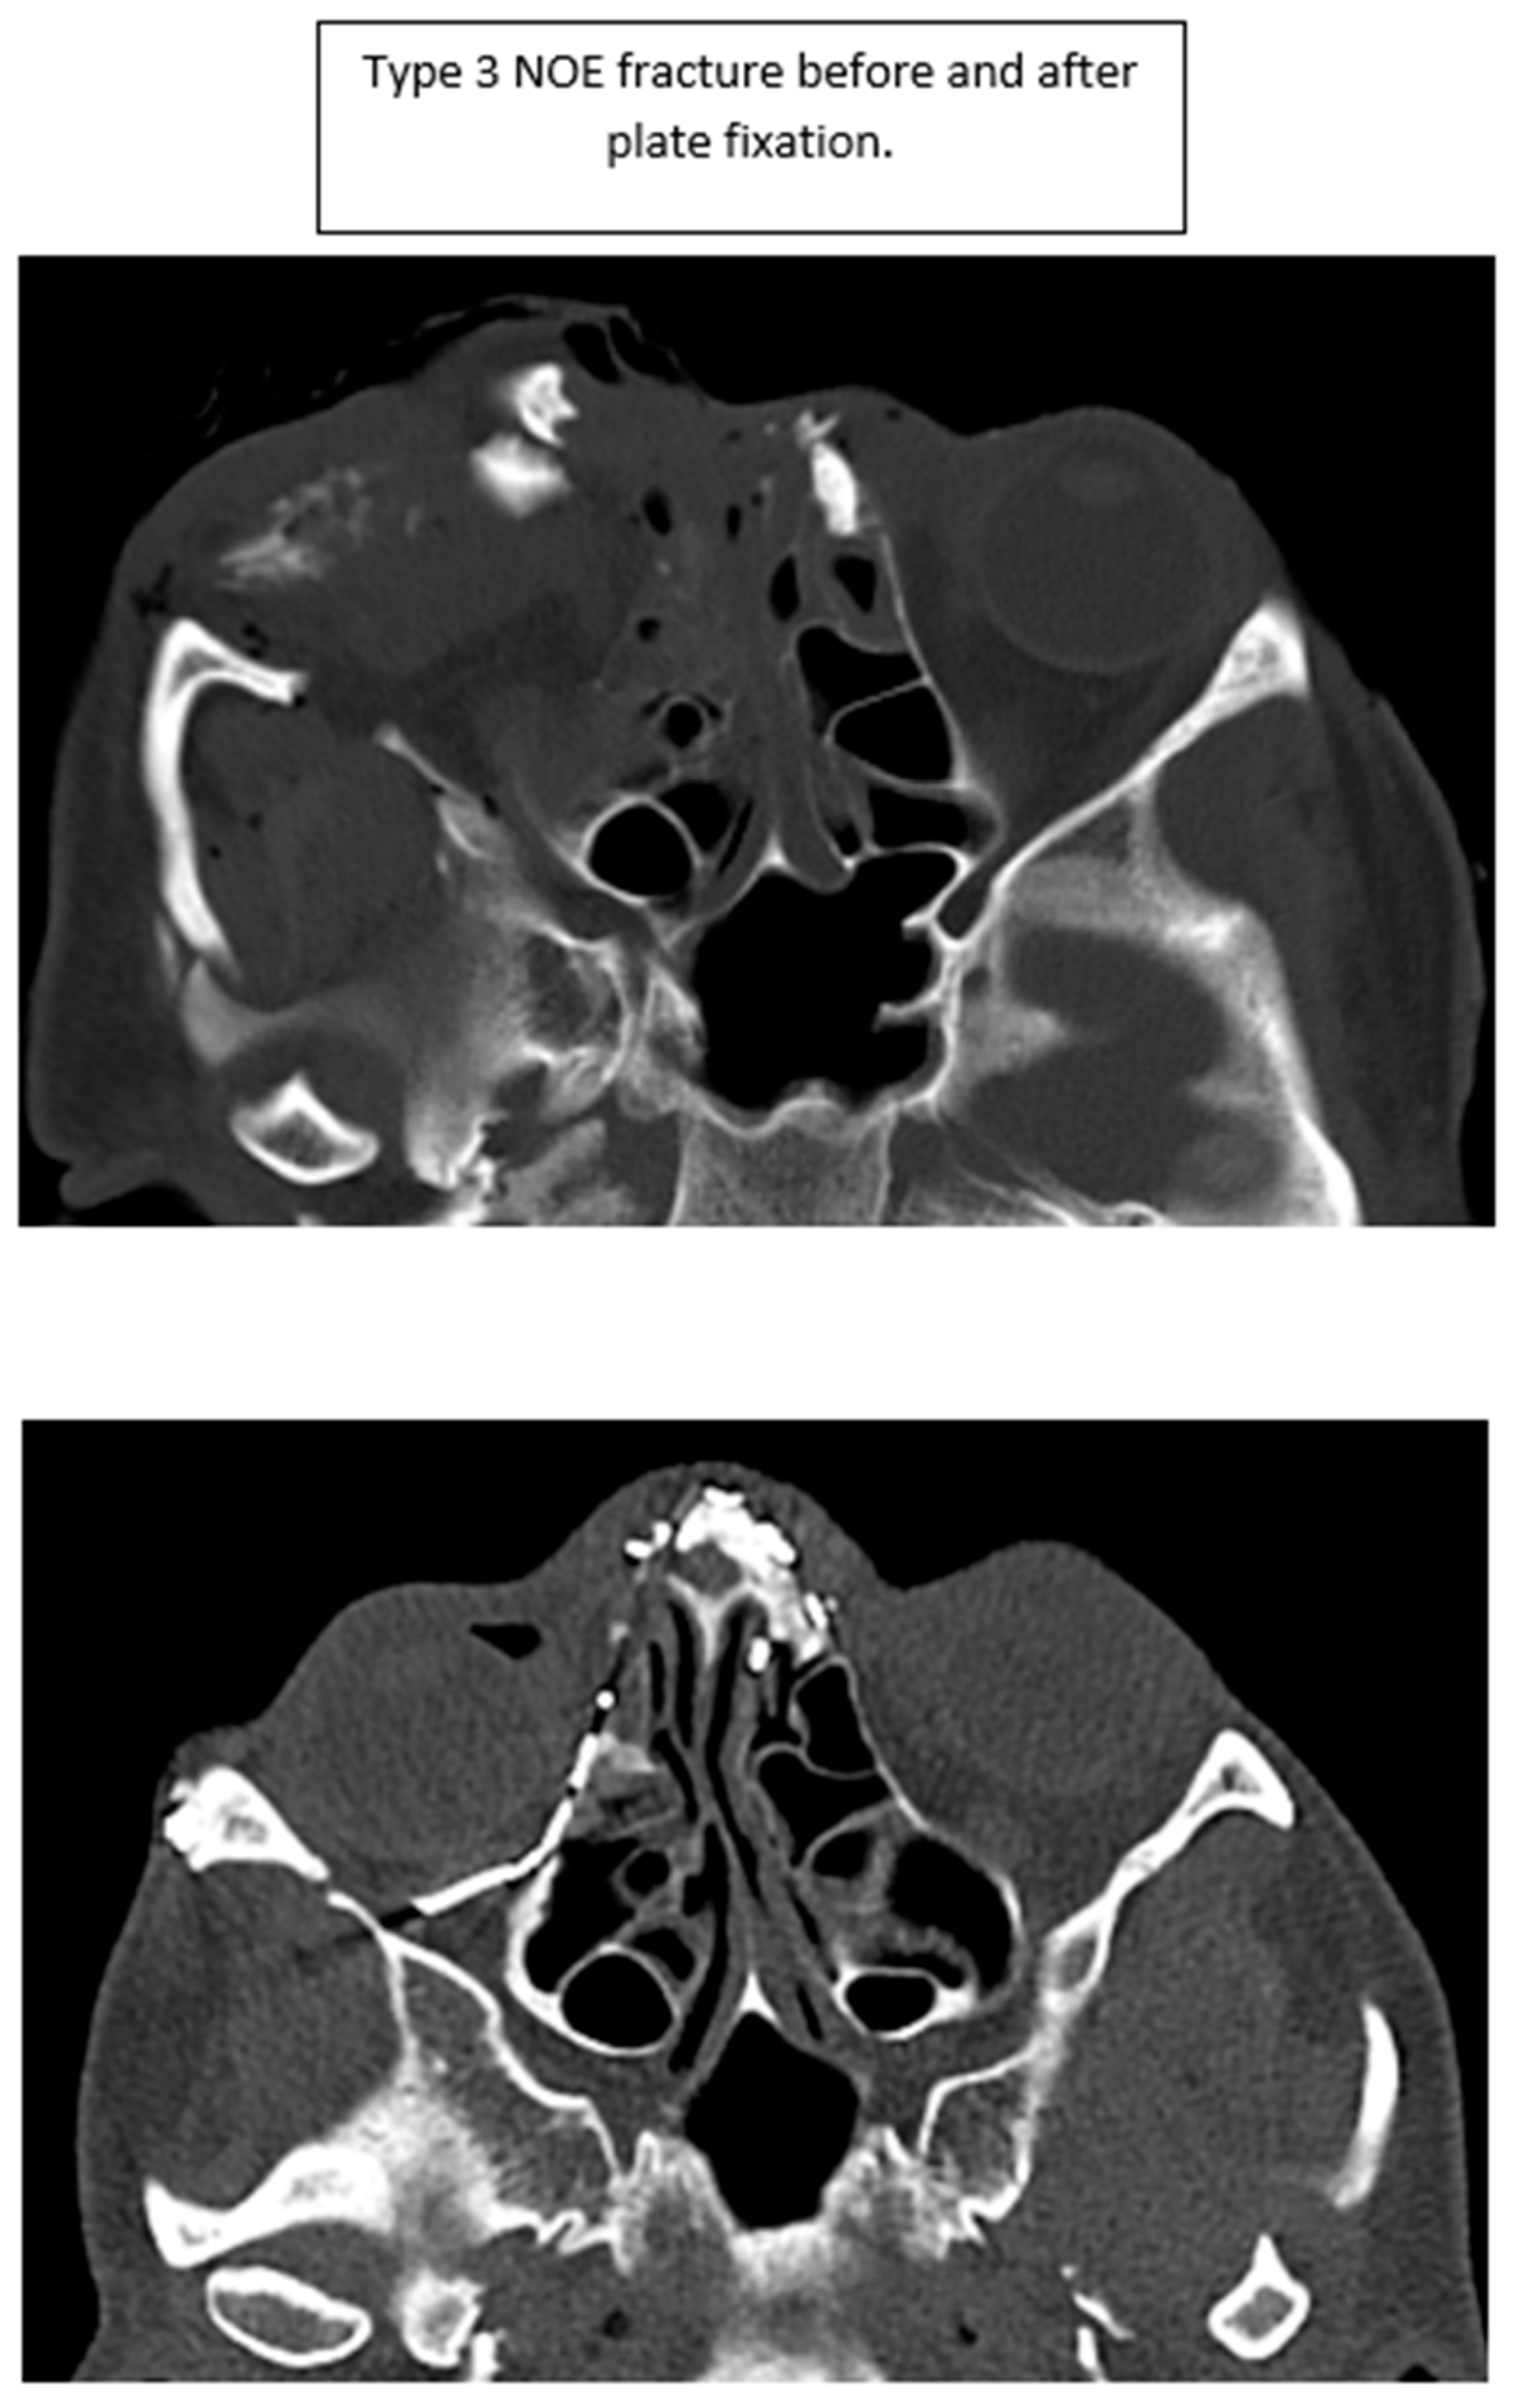

When available, intercanthal and interpupillary distances were measured on pre- and post-operative CT scans. All scans were reviewed and measured by the authors. When possible, the canthal fragment(s) were identified on pre-operative scans using both soft tissue and bone windows. The intercanthal distance was then measured on the scan. The measurements were then compared to the post-operative result. It was frequently necessary to identify the reduced canthal fragment on post-operative scans and then find it on the pre-operative scans for measurement, as this is not always readily identified. While this technically represents interfragmentary distance, the distance of the fragment was measured at the perceived site of the canthal tendon. Measurement error, if present, occurred in a consistent manner, producing reliable results. Representative images demonstrating this approach are shown in Figure 2.

Figure 2. Intercanthal distance measurement. (A) Pre-operative soft tissue imaging showing canthal tendons (stars). (B) Pre-operative bone windows showing measurement of intercanthal distance (line). (C) Post-operative soft tissue imaging of canthal tendons (stars). (D) Post-operative bone windows showing measurement of intercanthal distance (line).